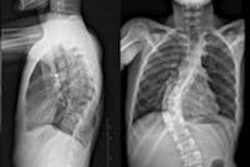

French digital radiography (DR) firm Biospace Med of Paris is touting the results of a clinical study that shows that the company's EOS DR system has better image quality and lower radiation dose than computed radiography (CR).

In the study, a team led by Dr. Stefan Parent, Ph.D., of the Centre Hospitalier Universitaire Sainte-Justine in Montreal compared Biospace Med's EOS system to a commercially available CR unit (FCR 7501S, Fujifilm Medical Systems USA, Stamford, CT) in a group of 50 patients with spinal deformities. Results of the study were published in the April 20 issue of Spine (Vol. 35:8, pp. E344-E346).

Patients with spinal deformities such as scoliosis often require multiple radiographs for follow-up throughout childhood and adolescence, a practice pattern that has caused concern due to radiation exposure, the authors noted. The EOS system uses a slot-scanning design that results in lower radiation dose, while producing 2D and 3D images that have more clinical potential that conventional DR, according to the authors.

The patient population consisted of 39 females and 11 males, with an average age of 14.8 ± 3.6 years. Each patient was imaged on both the EOS system and a CR unit, with studies performed 15 minutes apart. Dosimeters recorded radiation dose, and a panel of two orthopedists and two radiologists judged image quality.

Radiation dose produced by the EOS system was much lower than from the CR system, ranging from a ratio of 2.9 times less at the nape of the neck (0.20 mGy for the EOS unit compared to 0.59 mGy for CR) to 9.2 times less at the proximal anterosuperior iliac spine (0.16 mGy for EOS to 1.47 mGy for CR).

Images for the EOS system in terms of global image quality were rated as better than CR for 46.7% of cases, equivalent to CR in 50.5%, and worse than CR in 2.8%. In terms of structure visibility, EOS was rated as better than CR in 32.4% of cases, equivalent to CR in 61.9%, and worse in 5.7%.

The authors concluded that the EOS unit has better image quality with lower dose, and the system's potential to acquire 2D orthogonal images to facilitate 3D surface reconstruction of the vertebrae and pelvis could have potential.